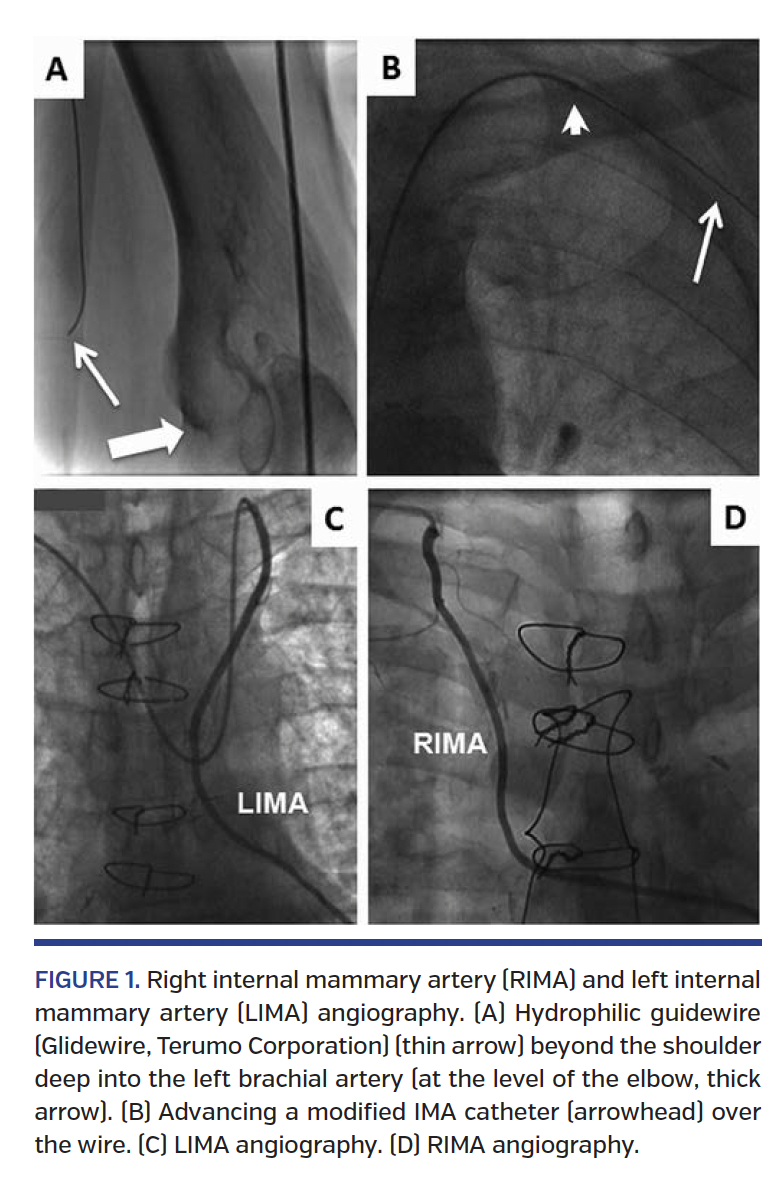

Internal mammary graft cannulation. The internal mammary artery (IMA) catheters, preferably the modified-IMA catheters, are a good choice. The modified-IMA catheter has a second curve proximally that permits an easier engagement and avoids backward motion (disengagement) while injecting. Also, it is useful for those patients presenting with a LIMA takeoff at the level of the ascending portion of the subclavian artery or at its corner toward the horizontal portion (this also applies to the RIMA). In cases where the left radial artery was surgically removed and used as a graft, the LIMA can be cannulated from the right wrist in more than 90% of cases. In order to provide enough support for advancing the catheter, it is crucial to place a 0.035˝ hydrophilic guidewire (eg, Glidewire; Terumo Corporation) beyond the shoulder, so “as far as possible” deep into the brachial artery (preferably at the level of the elbow; Figure 1A). This technique provides support for the advancement of the diagnostic catheter (eg, modified IMA, radial brachial, Tig) over the wire (Figure 1B). If it is not possible to advance the wire deep into the brachial artery, it is useless to try to advance the catheter since it will always flip back into the aorta. If there is not enough support to advance the catheter through the left subclavian artery, even with a proper deep wire placement, external compression of the left arm (brachial or radial/cubital artery) is advised in order to maintain/fix the wire and increase further support. This can also be achieved by inflating a blood pressure cuff or by the elbow flexion technique.5